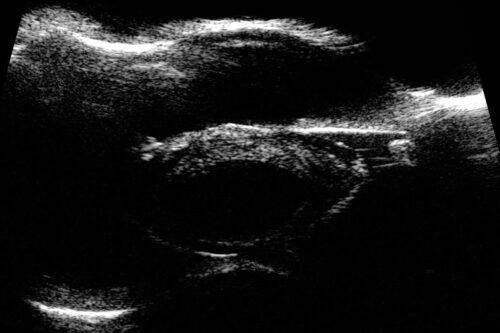

Low noise, high performance

In posterior B-Scan mode, Eye One’s industry leading signal-to-noise ratio means it’s able to detect the subtlest vitreous echoes, offering unparalleled distinction and diagnosis accuracy across the retina, choroid, sclera, and the vitreo retinal junction.